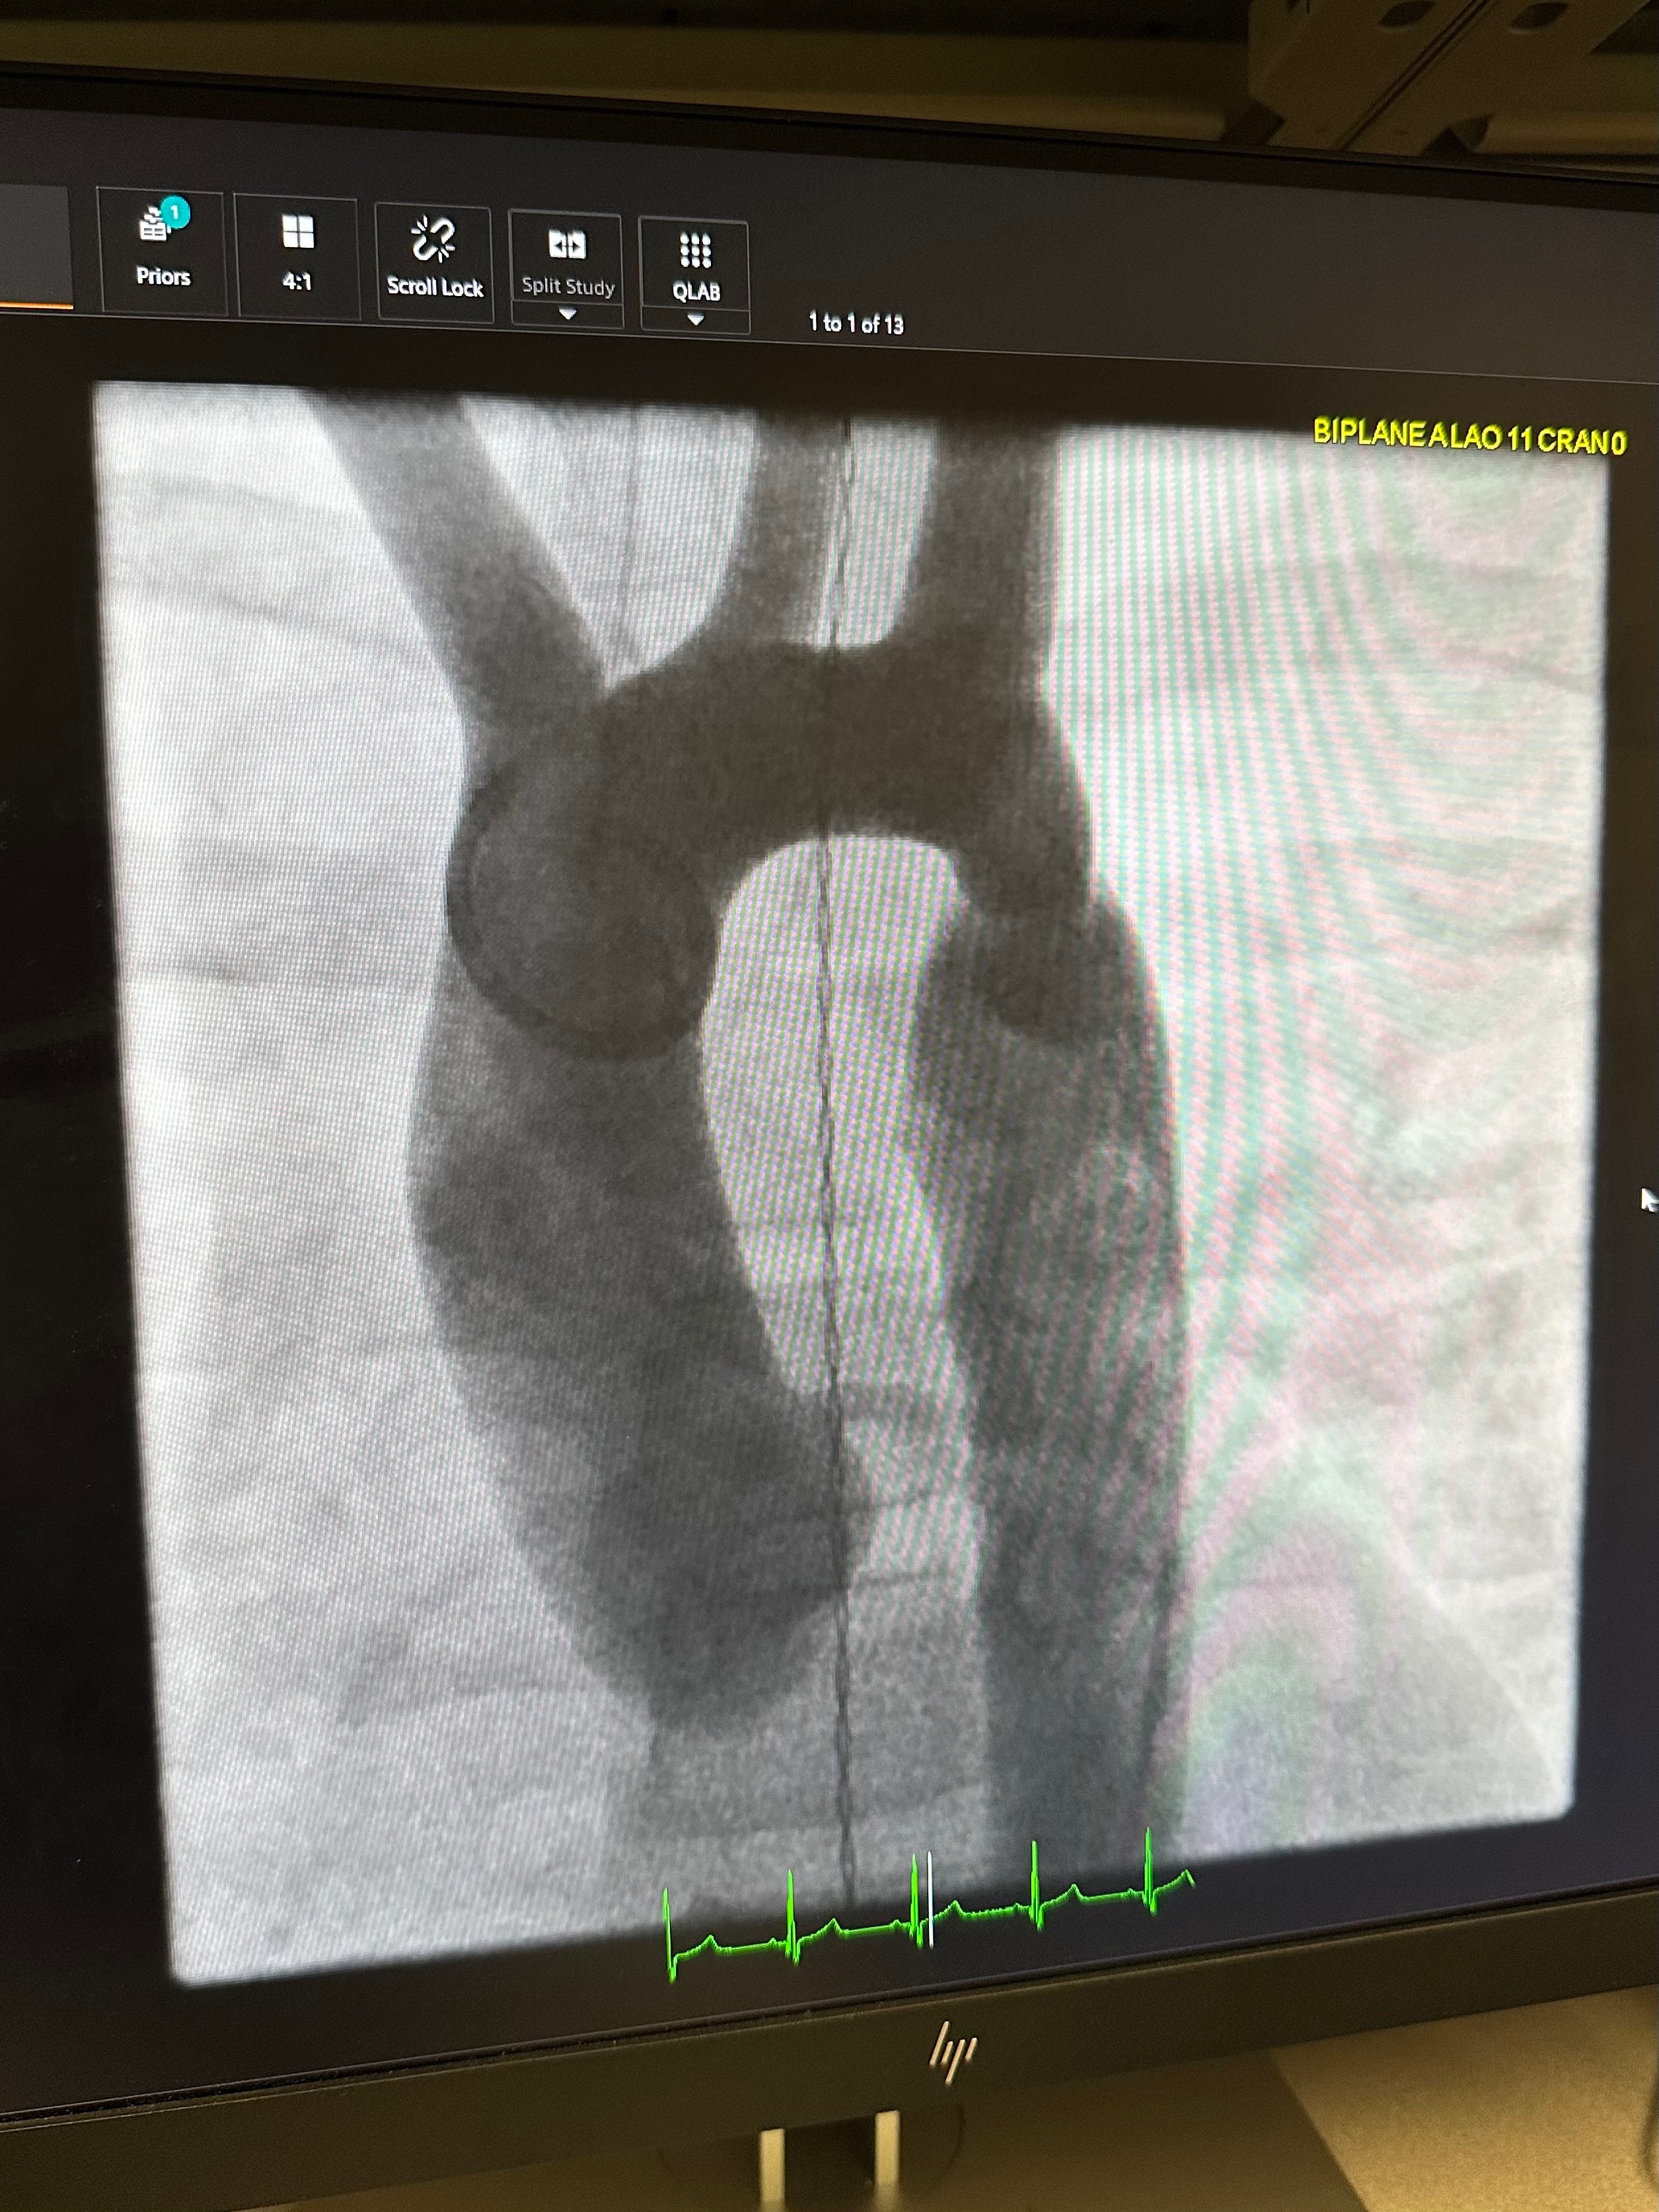

1. Coarctation of the Aorta – A life-threatening narrowing of her main artery

Instead, they made new plans to do a small incision in her thigh and go in with a balloon and stent to gently open the main narrowed artery.

No cutting through bone, rib separation or significant blood loss.

Just a small incision, breath, expansion, and a rod of support.

We’re happy to share that Saphira’s heart surgery went smoothly, and she is now back home recovering! The procedure was successful, and we only had to spend one night at Primary Children’s. The care team were absolutely incredible, and we felt held and supported throughout the entire process.

There is still a healing journey ahead. Saphira continues to have two congenital heart defects that may cause future complications with her development. While that reality is heavy, we’re grateful the doctors feel confident she’ll be able to return to her usual activities within 2–4 weeks.